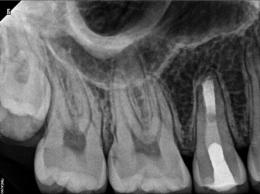

Every tooth has different numbers of roots and canal systems. With the help of magnification and high tech equipment, Dr. Jung can locate and treat the canals including MB2 on upper molars and MM on lower molars.